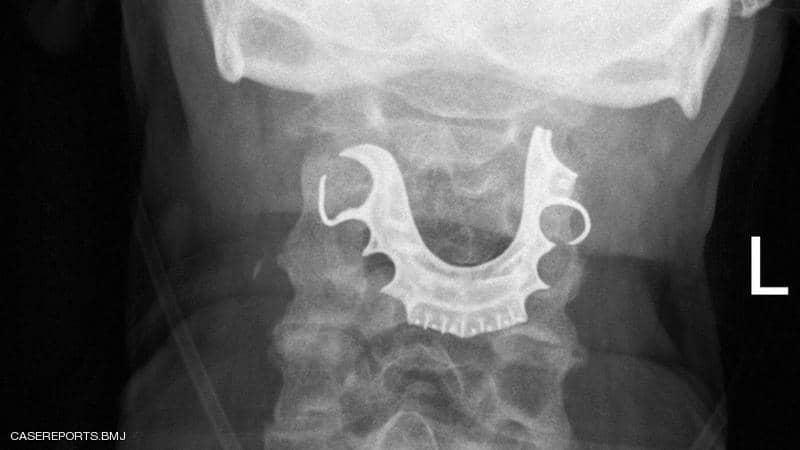

وعندما خضع للفحص، اكتشف الأطباء وجود جسم نصف دائري في حلقه حول الأحبال الصوتية، مما أدى إلى التهابات داخلية، وأثبتت الأشعة الضوئية أن هذا الجسم هو طاقم الأسنان.